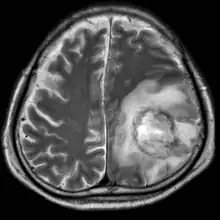

| T2-weighted MRI showing a necrotic brain abscess as a result of GAE caused by an infection of Acanthamoeba. | |